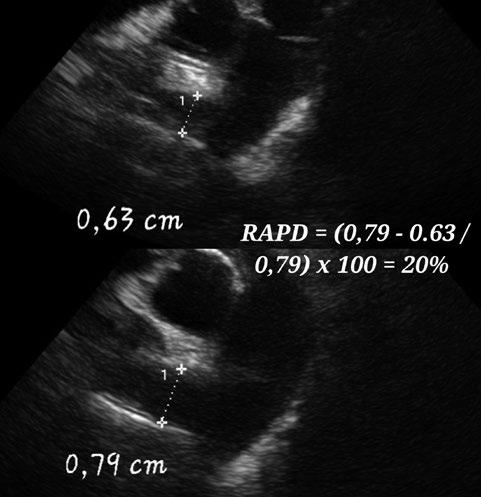

Bloqueantes de canales del calcio Hidralazina, nitratos e IECA